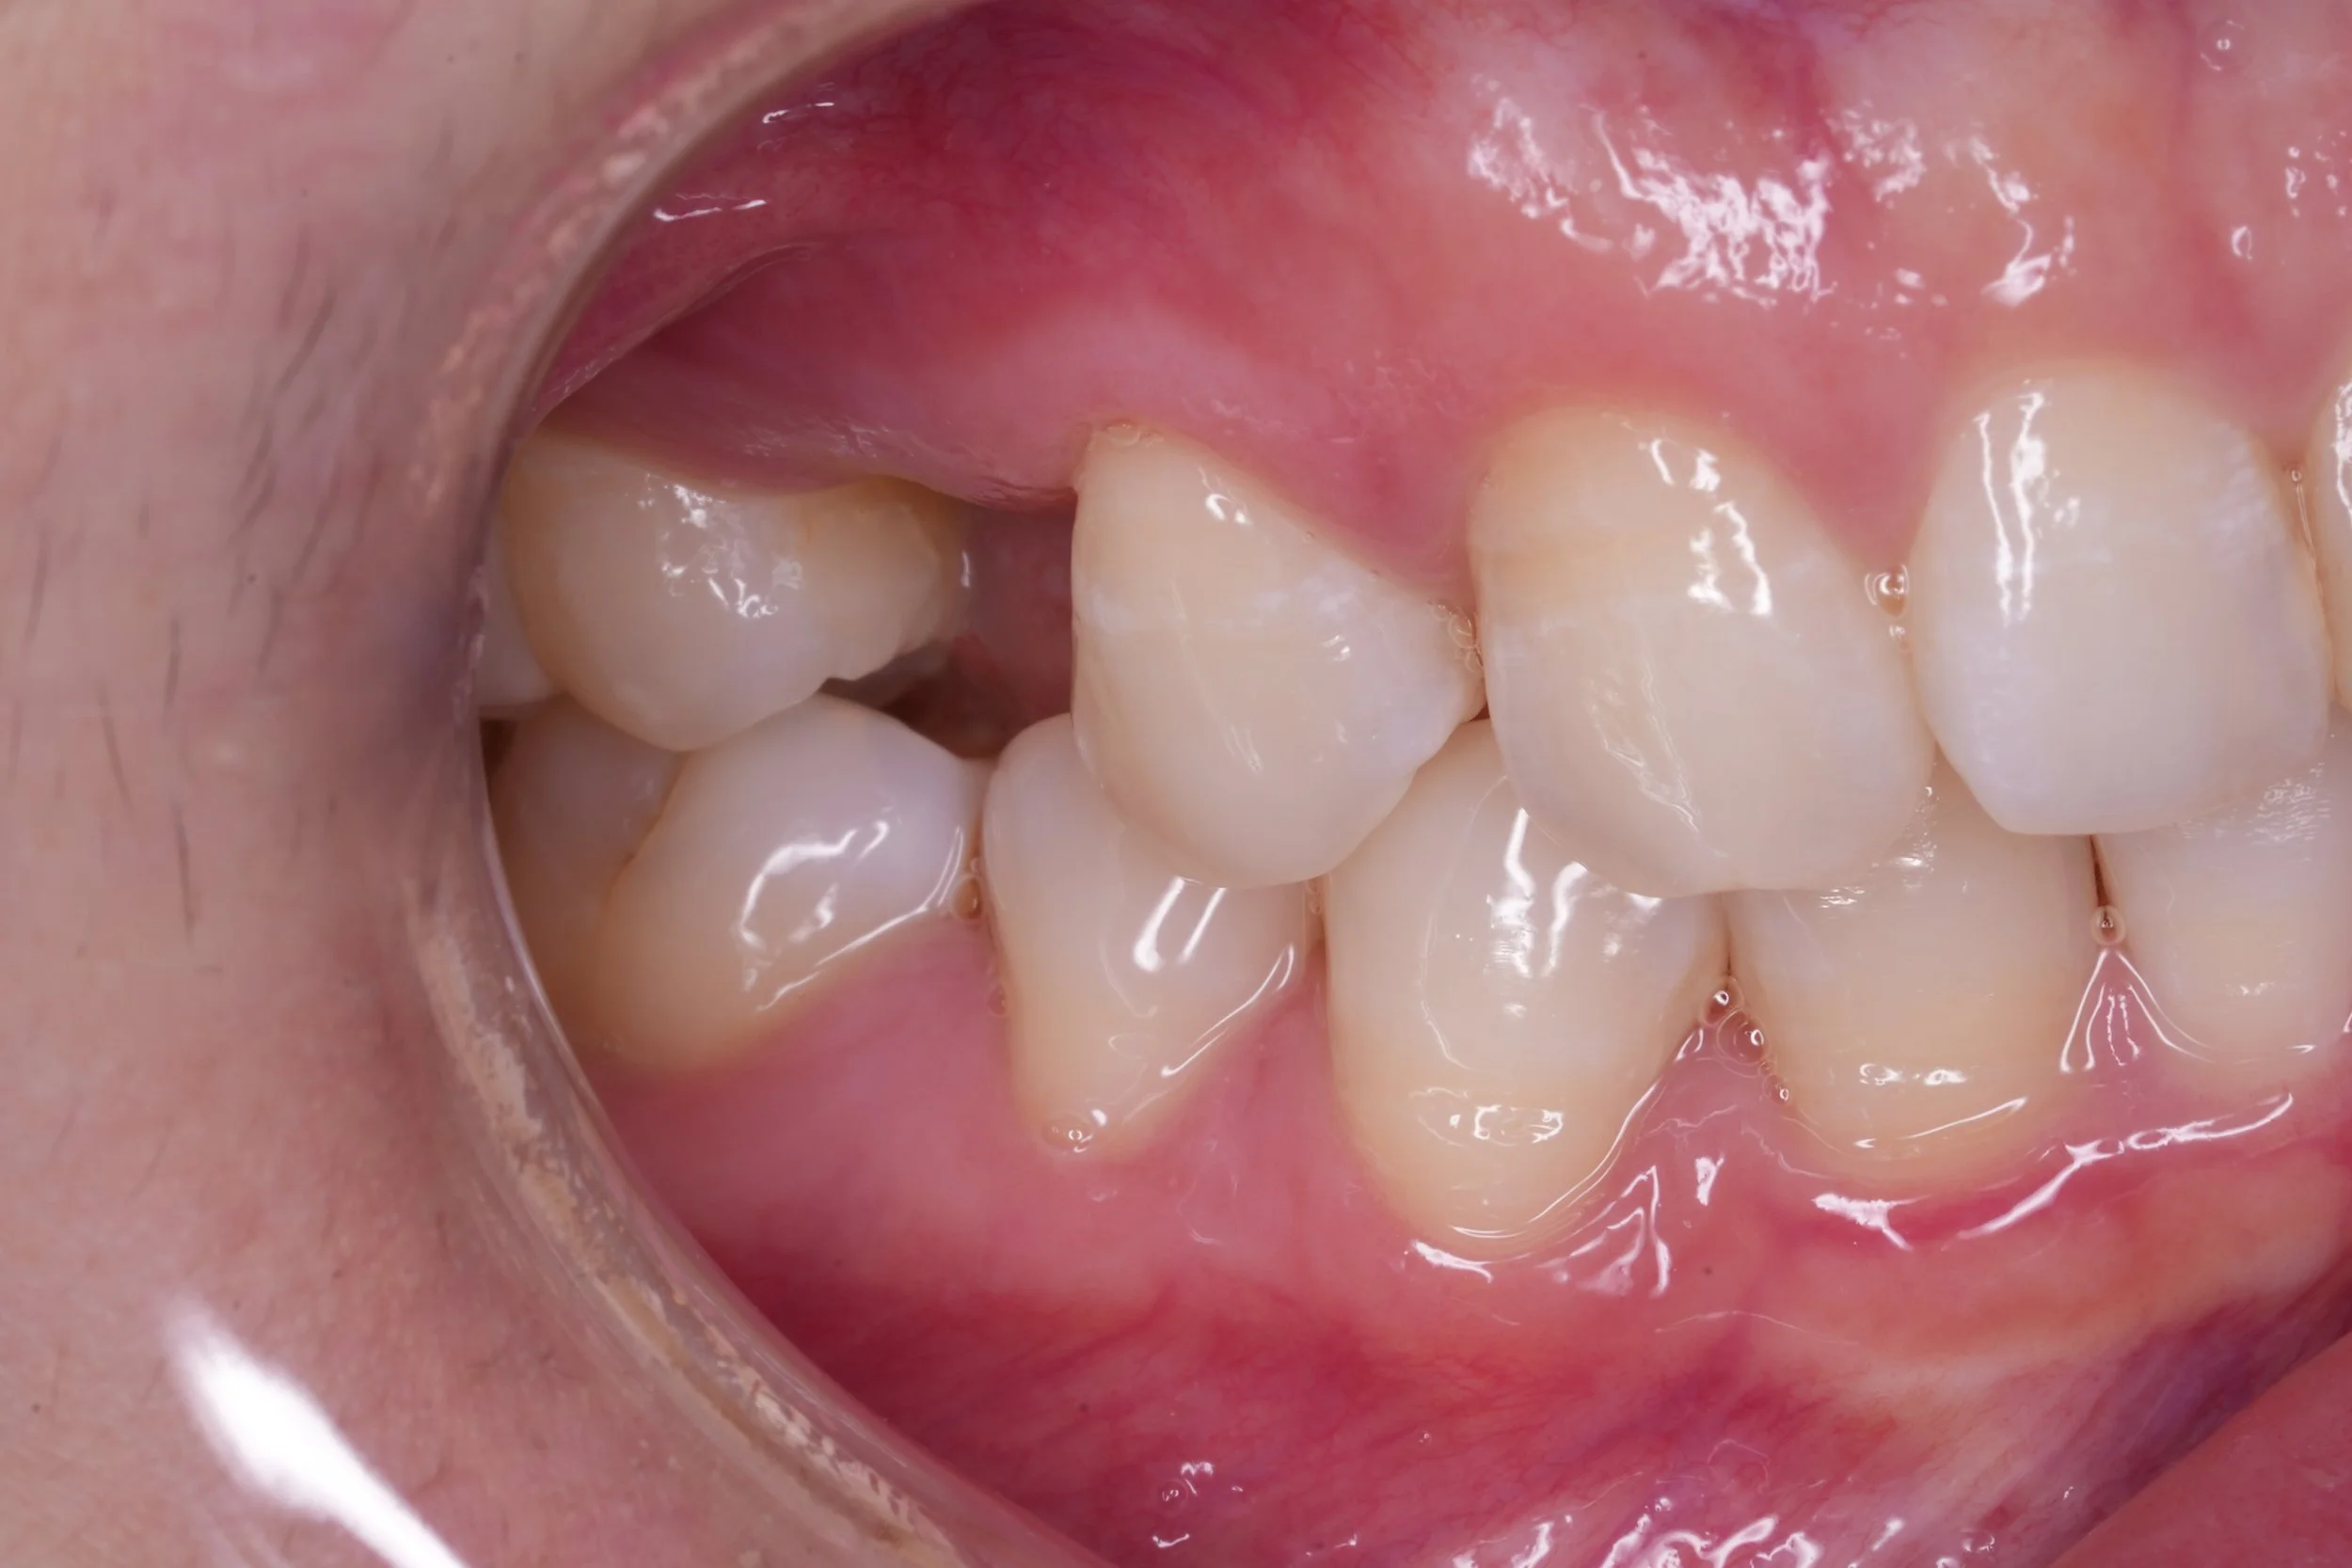

Fixed pros

Dental Implants